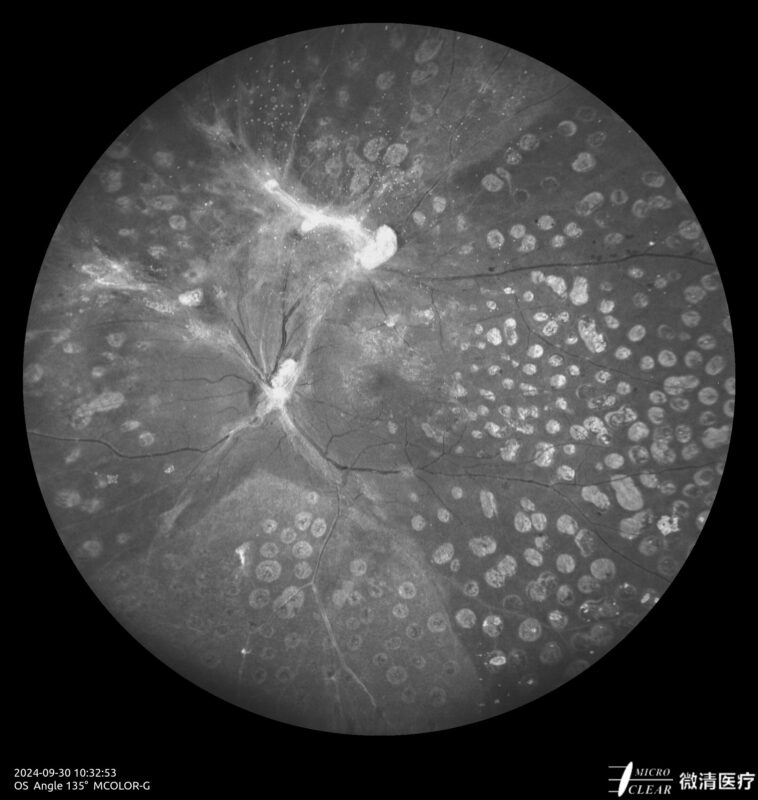

Ultra-groothoek en multimodale fundusangiografie gebaseerd op confocale scanning laser oftalmoscopie (CSLO).

- 135° WA (Groothoekangiografie) – in één opname